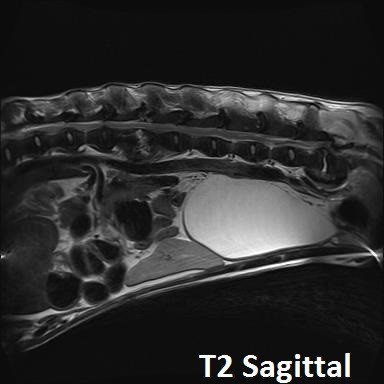

Orthogonale opnamen van de lumbale wervelkolom zijn beschikbaar voor interpretatie.

Er is een uitgesproken onregelmatigheid van de caudale eindplaat van L2 en de craniale eindplaat van L3, met vernauwing van de tussenwervelschijf L2-L3 en matige spondylosis deformans op dit niveau.

Er is vernauwing van de tussenwervelschijf L7-S1 met sclerose van de aangrenzende eindplaten en spondylosis deformans op dit niveau.